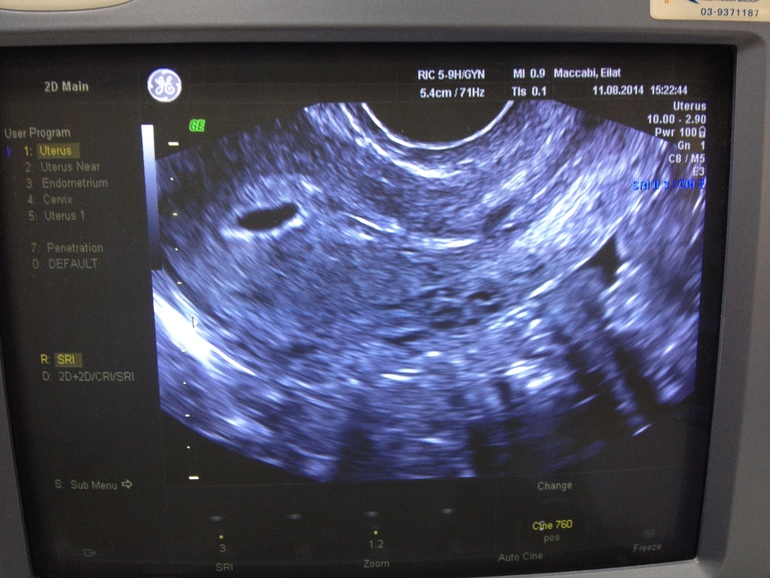

узи 5 недель и 2 дня

Вопросы про УЗИ, обследования и анализы: что, где, как, когда?девочки подскажите, пожалуйста, насчет узи. Сегодня была у врача, но он мне ничего толком не сказал кроме "приди через неделю" а я ничего не понимаю по этой фотке. понимаю только что эмбриончика не видно, нормально ли это? может просто слишком рано? я даже не очень понимаю где границы матки...девочки скажите ваше мнение!

Для эмбриона еще рано, ПЯ высоко — это хорошо=) (если смотреть, то верх матки слева, шейка — справа) некруглое, потому что ракурс такой взят.

Плодное яйцо видно, а ембриончика ещё не видно. У меня ембриончик стал виден на 8 неделе. Все ещё впереди, не переживайте.

Да, в левом верхнем углу плодное яйцо, а эмбриона еще нет. Срок еще маленький, не волнуйтесь

У меня в 5 недель было только ПЯ 7 мм. Через две недели уже был эмбрион и сердцебиение.